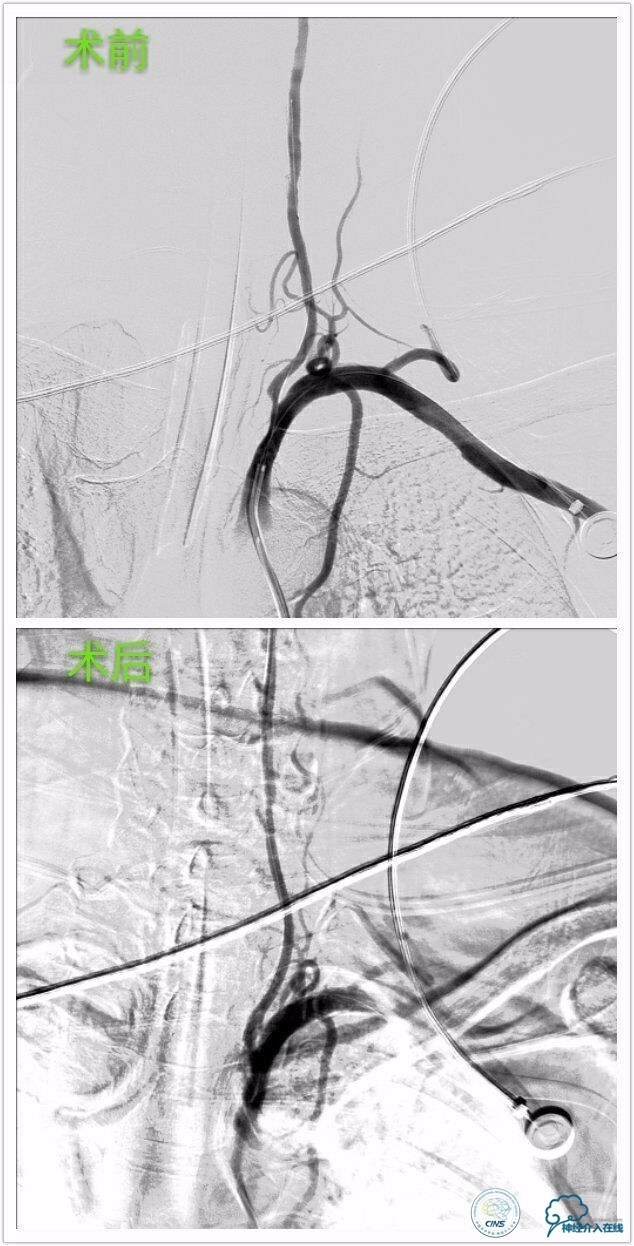

行脑血管造影见:左侧颈内动脉交通段重度狭窄,左侧椎动脉开口重度狭窄,前交通、大脑前动脉、大脑后远端血管有部分代偿,左侧大脑中动脉区域侧支代偿不足。

行左侧颈内交通段、左椎开口支架成形术治疗。

》左侧颈内交通段球囊扩张支架成形术:

》左侧椎动脉开口球囊扩张支架成形术: